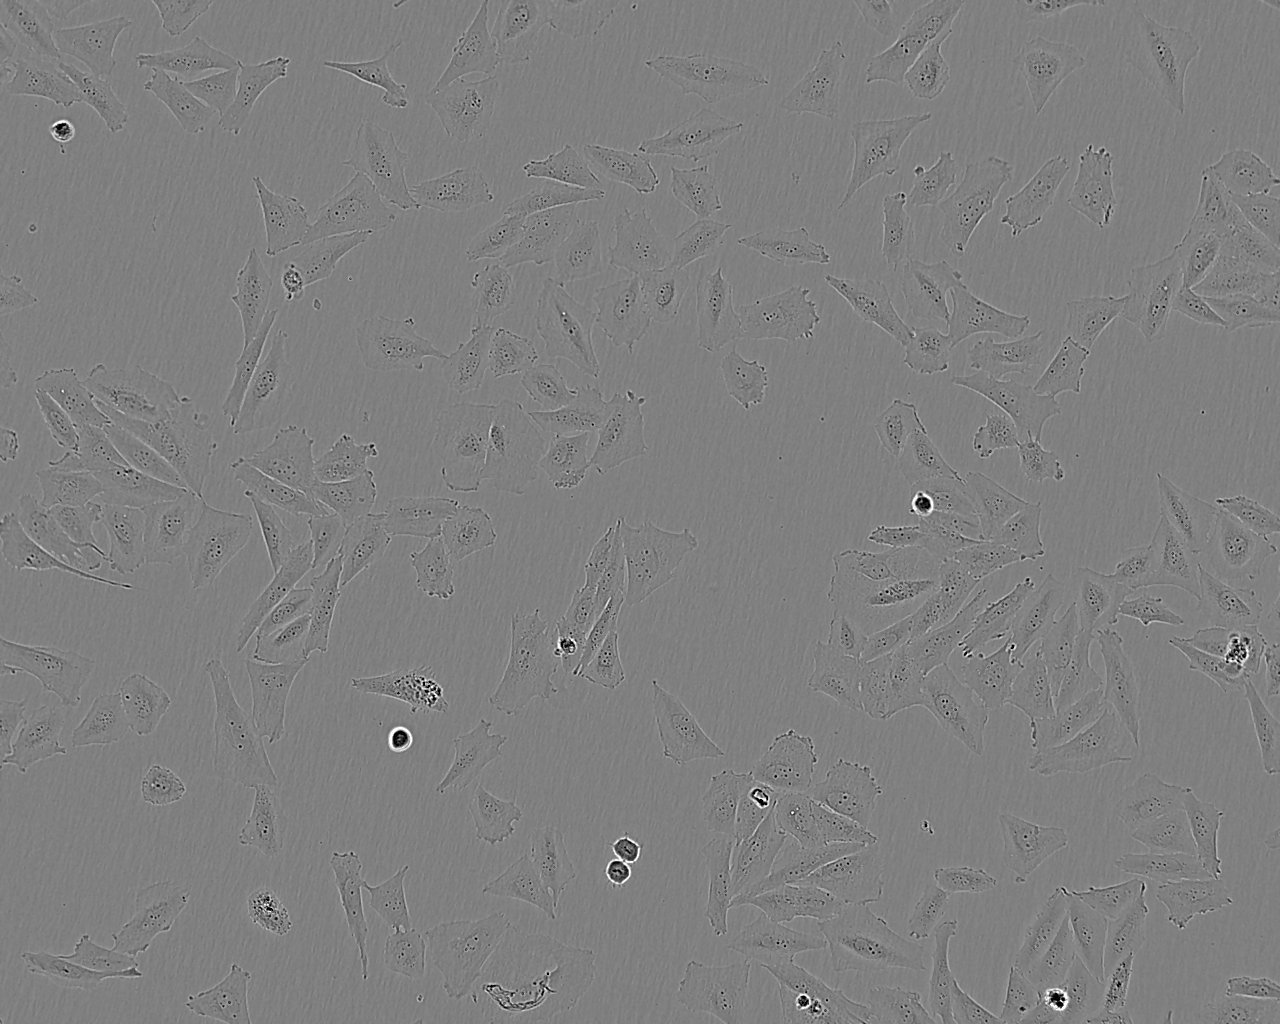

Cell Type

Epithelial-like

Growth Mode

Adherent